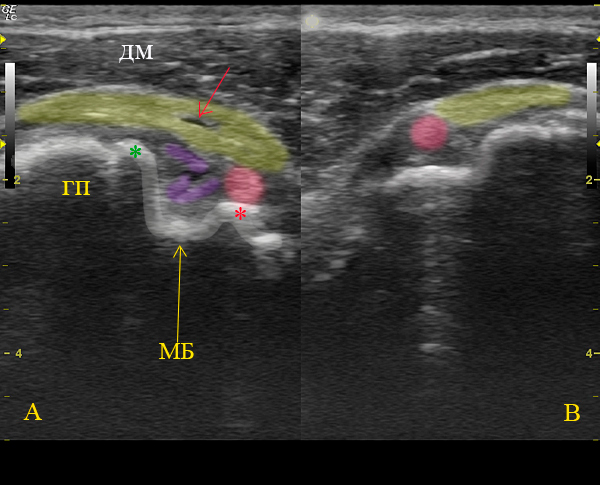

Да, на последней сонограмме В+В: А - сонограмма с патологией, В - таже проекция в здоровом противоположном плечевом суставе.

Вот такой получился у меня расклад данного уз-случая.

А:

ГП - головка плечевой кости,МБ - межбугорковая борозда, ДМ- двухглавая мышца,

розовая зона - дислоцированное на уровень малого бугорка сухожилие длинной головки бицепса,

фиолетовая зона - фрагменты поперечной связки плеча, которая образована волокнами из передней поверхности сухожилия подлопаточной мышцы, желтая зона - сухожилие надостной мышцы с участком частичного, линейного разрыва сухожилия.

В:

Сонограмма здорового контролатерального плечевого сустава, представлена для сравнения нормального расположения сухожилия длинной головки бицепса в межбугорковой борозде.

А что показано красной стрелкой и окончательное заключение?